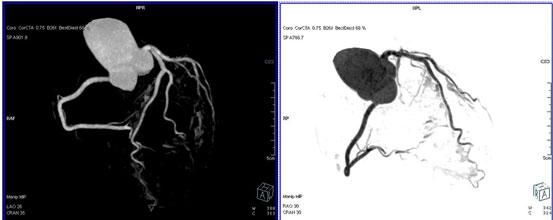

二、多層螺旋CT頭頸部及體部血管成像技術:

該機掃描覆蓋範圍廣、時間短,多種後處理分析軟件能顯示各血管細小分支,可以清晰顯示動脈瘤、動脈夾層、血管畸形、血管狹窄及動脈粥樣硬化斑塊等,适用于頭頸部血管成像、肺動脈成像、胸腹部血管成像及四肢血管成像。

1.顱腦血管成像:

動脈瘤

2、頸部血管成像

3、肺動脈血管成像:

4、腎動脈血管成像(腎動脈狹窄):

5、下肢動脈血管成像: